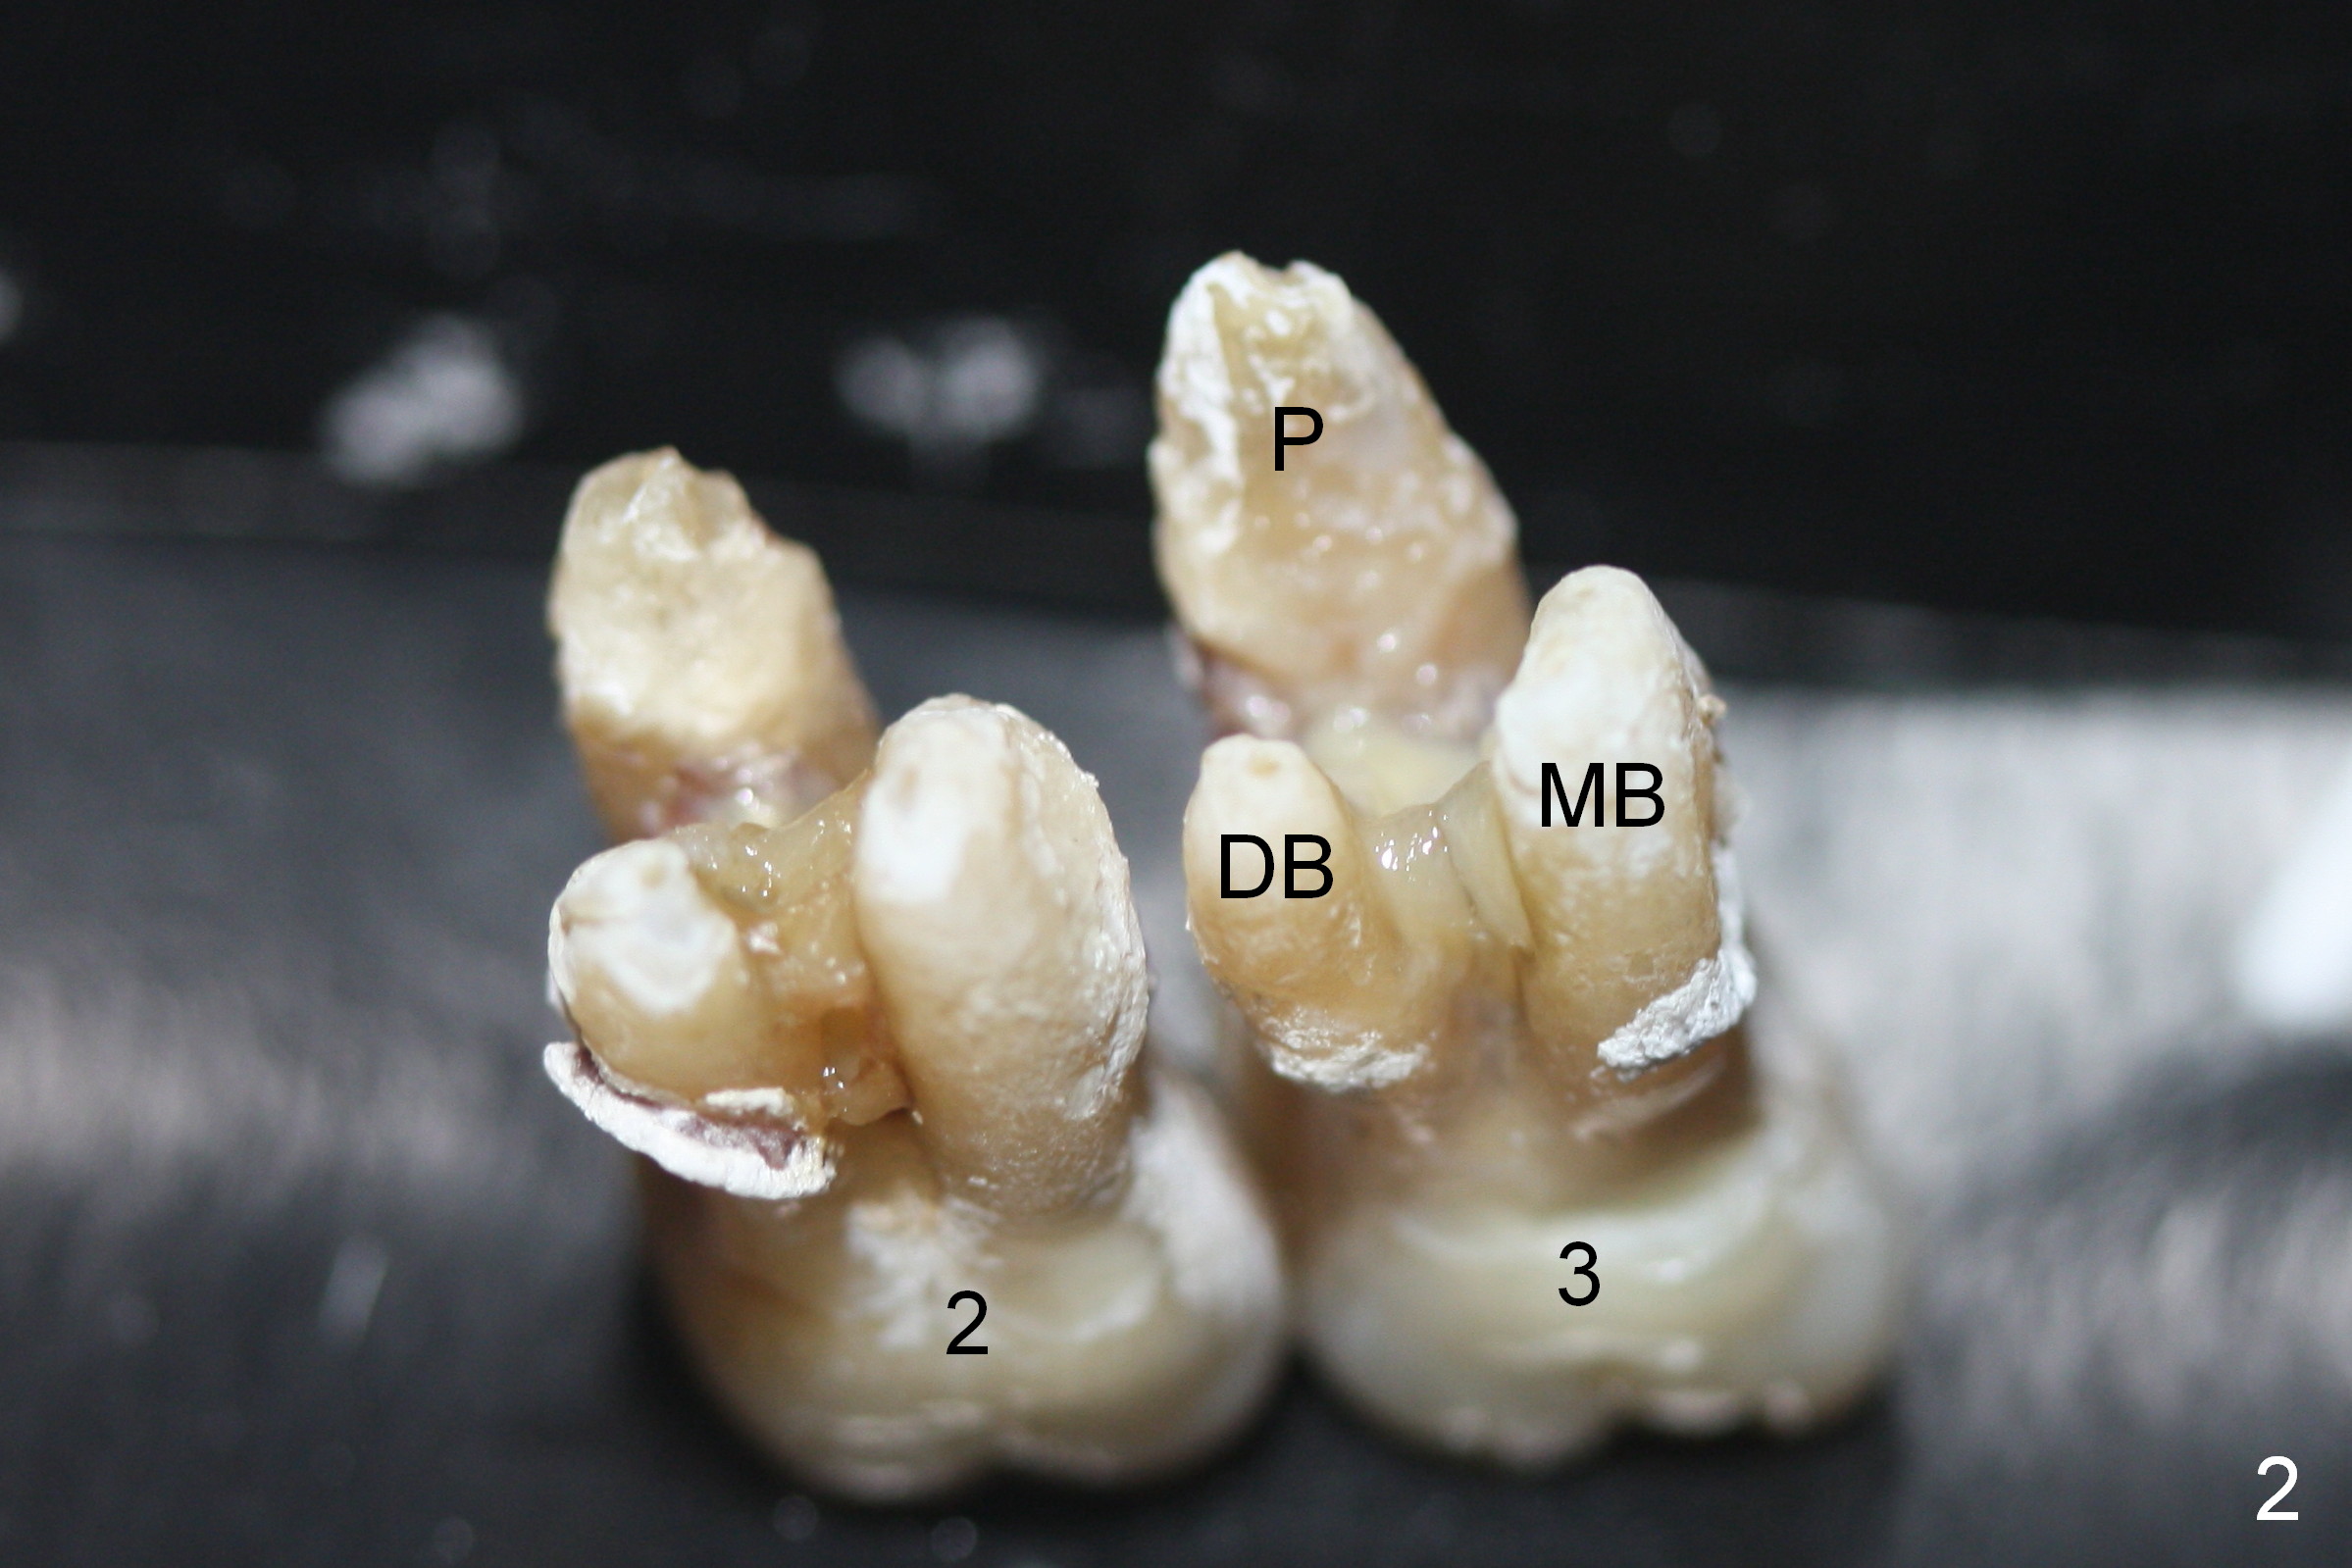

The maxillary 1st molar has 3 widely separated roots (Fig.1-3: #3) with a wide septum in between, as compared to the 2nd one (#2). The septum is a suitable site of immediate implant. When the septum is destroyed by pathology, the immediate implant has to be big.